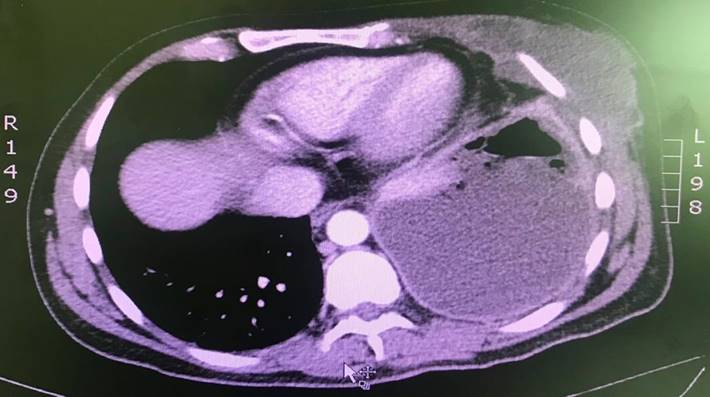

Ante los hallazgos en la radiografía simple, se decidió complementar el estudio con una TAC de tórax con contraste, que reportó colecciones pleurales bilaterales con extensión a la pared del tórax (con compromiso de la musculatura intercostal y escalénica en el lado derecho; en el lado izquierdo estaba comprometido el pectoral) en relación con Empiema Necessitatis (Figura 3, Figura 4).

El paciente es evaluado por cirugía de tórax que realizó pleurectomía y decorticación por videotoracoscopia e inició antibiótico. Durante el intraoperatorio, en el lado izquierdo se drenan 500 cc aproximadamente de material purulento del plano subcutáneo y 600 cc de pus franca de la cavidad pleural. En lado derecho se drenan 200 cc de pus franca loculada de la cavidad pleural, con compromiso del plano muscular y costal. El paciente permaneció hospitalizado por 17 días. De los cultivos se aisló S. aureus sensible. El paciente recibió oxacilina. Fue dado de alta con cefazolina.